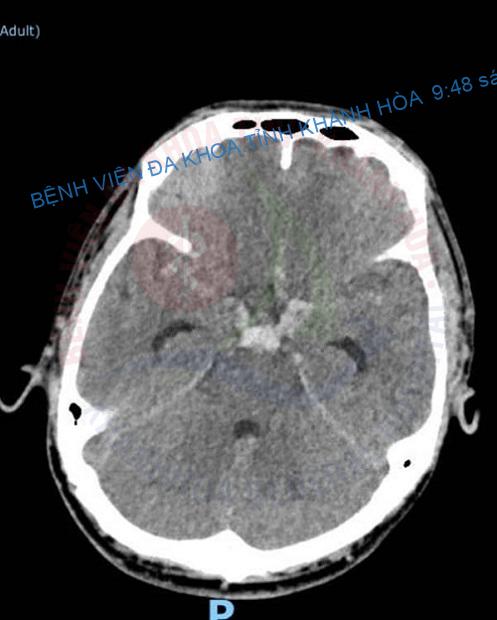

Theo đó bệnh nhân nam, 43 tuổi vào viện với chẩn đoán: xuất huyết dưới nhện lan toả sau tai nạn. Qua khai thác tiền sử, bệnh sử và thăm khám lâm sàng, bệnh nhân được chẩn đoán sơ bộ xuất huyết dưới nhện lan toả do chấn thương, cần phân biệt với xuất huyết dưới nhện tự phát do túi phình mạch não vỡ. Sau hội chẩn, các bác sĩ tiến hành chụp cắt lớp vi tính mạch não (CTA) đánh giá tổn thương. Kết quả chụp ghi nhận bệnh nhân có túi phình động mạch đốt sống bên phải trên vị trí xuất phát của động mạch tiểu não trên (SCA) phải, dạng hình bọng nước, có nhú vỡ ở đỉnh.

Đánh giá đây là một trường hợp khó, nguy cơ cao và là cấp cứu ngoại khoa, bệnh nhân đã được tiến hành điều trị bằng can thiệp nội mạch làm tắc túi phình. Thủ thuật này được thực hiện bởi các bác sĩ Khoa Ngoại Thần kinh – Bệnh viện Đa khoa tỉnh Khánh Hoà với sự hỗ trợ chuyên môn từ Bác sĩ Trần Quốc Tuấn – Trưởng Đơn vị Can thiệp Nội mạch Thần kinh, Bệnh viện Đại học Y Dược Thành phố Hồ Chí Minh. Sau 3 giờ với kỹ thuật đặt stent đổi hướng dòng chảy (flow diverted) và coiling bảo vệ đáy túi phình, tình trạng bệnh nhân dần ổn định và được xuất viện.